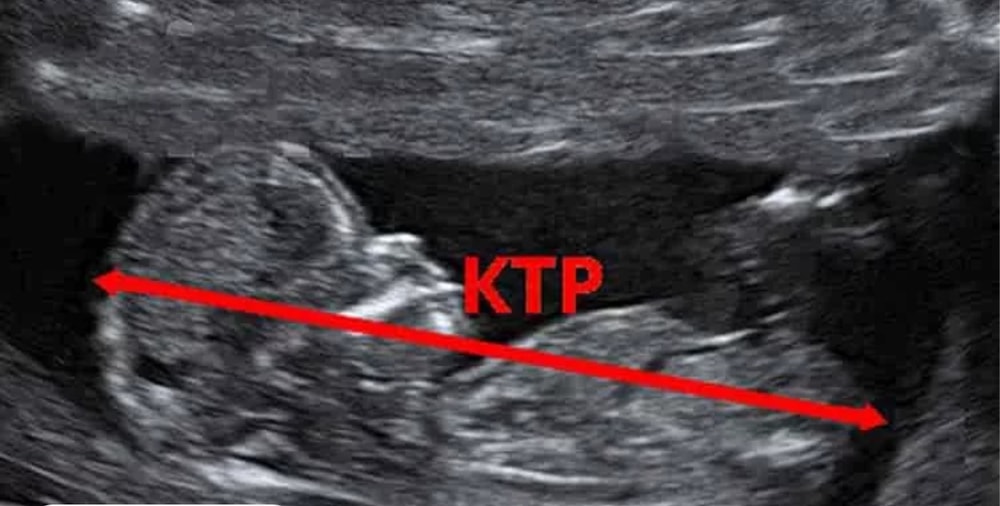

Abigeil

Алиса, КТР измеряется в саггитальном срезе

Вот так👇

А не то что вам намерили. Не удивительно, что погрешность плюс минус километр 🙃